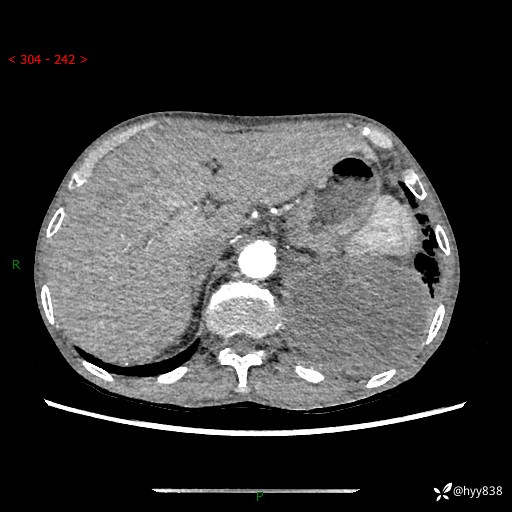

77岁/男,腹痛2月,CT发现左肺占位1天。巨大肿块,肺内或肺外来源…结果公布~

主诉:腹痛2月,CT发现左肺占位1天

现病史:患者于2025年9月间断左下腹胀痛,在当地镇卫生院行彩超检查考虑泌尿系结石,行止痛排石对症治疗未见明显好转;1天前腹痛症状加重,至当地市第三人民医院行CT检查:左肺下叶巨大团块状软组织影,考虑肿瘤性病变,建议增强CT检查;左侧胸腔积液;纵膈内淋巴结肿大;双肺肺气肿;右肺中叶纤维灶。为进一步求治,来我院就诊。

胸部CT平扫+增强